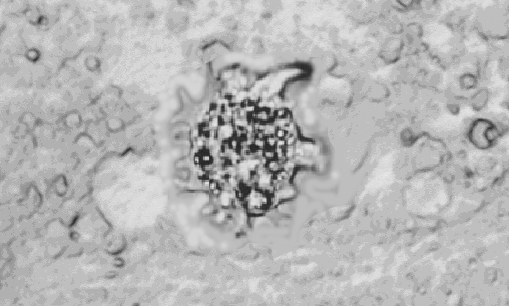

При микроскопическом исследовании на живом материале и на срезах пораженных жабр карпов были обнаружены образования, не встречающиеся на жабрах здоровых рыб. В побелевших и отекших концах жаберных лепестков находили большое количество мелких одноклеточных амебоидов, которые двигались (рис. 1). Они образовывали пальцевидные или сосочковидные псевоподии, которые отходили от широких лопастей (при изучении живых амеб). При исследовании с помощью сканирующего электронного микроскопа (рис. 2) было видно, что трофозоиты имели большую длину, чем ширину. Плотная кутикула, размеры тела, размеры (длина между 13-26 µм, соотношение длины к ширине 1,0-2,4) и другие морфологические признаки позволяют отнести данный организм к роду Mayorella сем. Paramoebidae.

Рис. 1. а. Жабры больных карпов: 1 гиперплазия жаберного эпителия (х 400); б. Зернистые амебоиды из жаберных лепестков больных карпов (х 480)

Рис. 2. Mayorella sp. с жабр карпа (сканирующий электронный микроскоп)

Помимо морфофункциональных нарушений в жабрах регистрировались образования, похожие на амебоидов. Одни - удлиненной овальной формы, с уплотненной оболочкой и плотной, ярко окрашенной цитоплазмой. Другие - округлой формы, с прозрачной цитоплазмой, средней плотности оболочкой и хорошо различимыми органеллами. Также были обнаружены очень крупные новообразования, одетые толстой оболочкой и содержащие конгломераты.